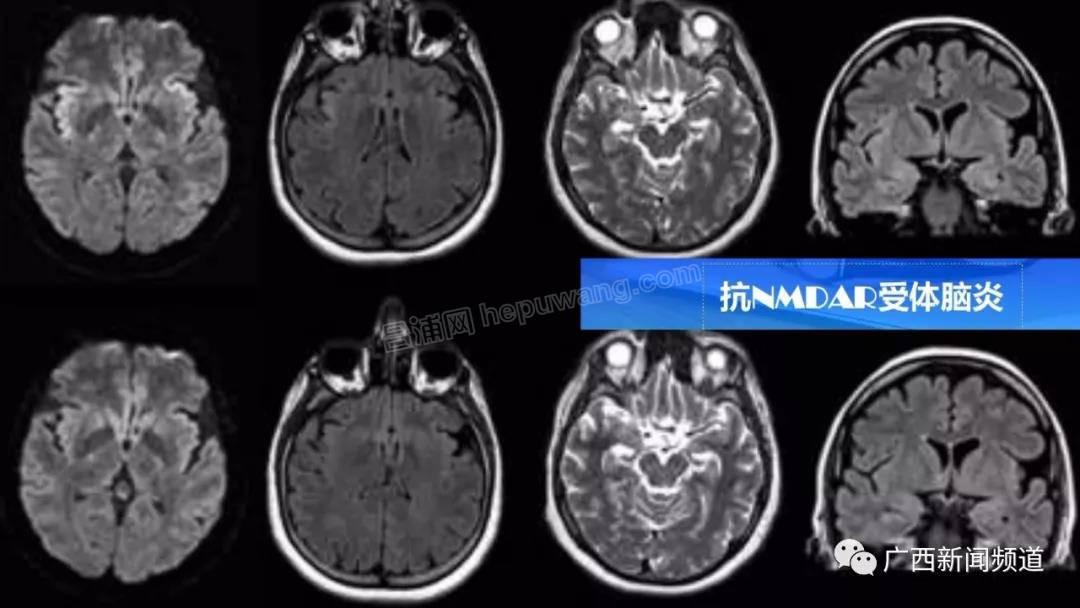

南宁市第一人民医院儿科二区主任  曹棨:自身免疫性脑炎今年我们科室已经发现4例了。它是由于自身的免疫系统失控了,在大脑里面产生一种抗体,自己杀伤自己的神经细胞。最容易误诊为精神病。